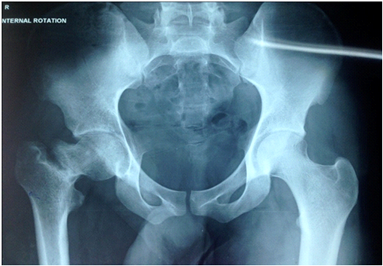

The patient began active exercises of the hip and knee immediately thereafter and began using crutches within the first 24 hours of surgery. Weight bearing was delayed until healing was seen at the osteotomy site on radiographs, usually about 6 weeks, and thereafter progressed gradually to full weight bearing, as tolerated.Patient was followed at every three month till one year. To review the results, the Harris numerical review system was used (Figure 4).

Figure 4 Post operative radiograph at 1 year of follow up.